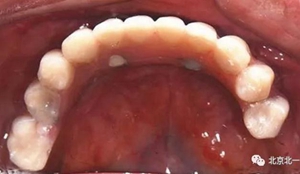

圖十九:永久修復(fù)完成

圖二十:永久修復(fù)咬合關(guān)系

圖二十五:口內(nèi)照。